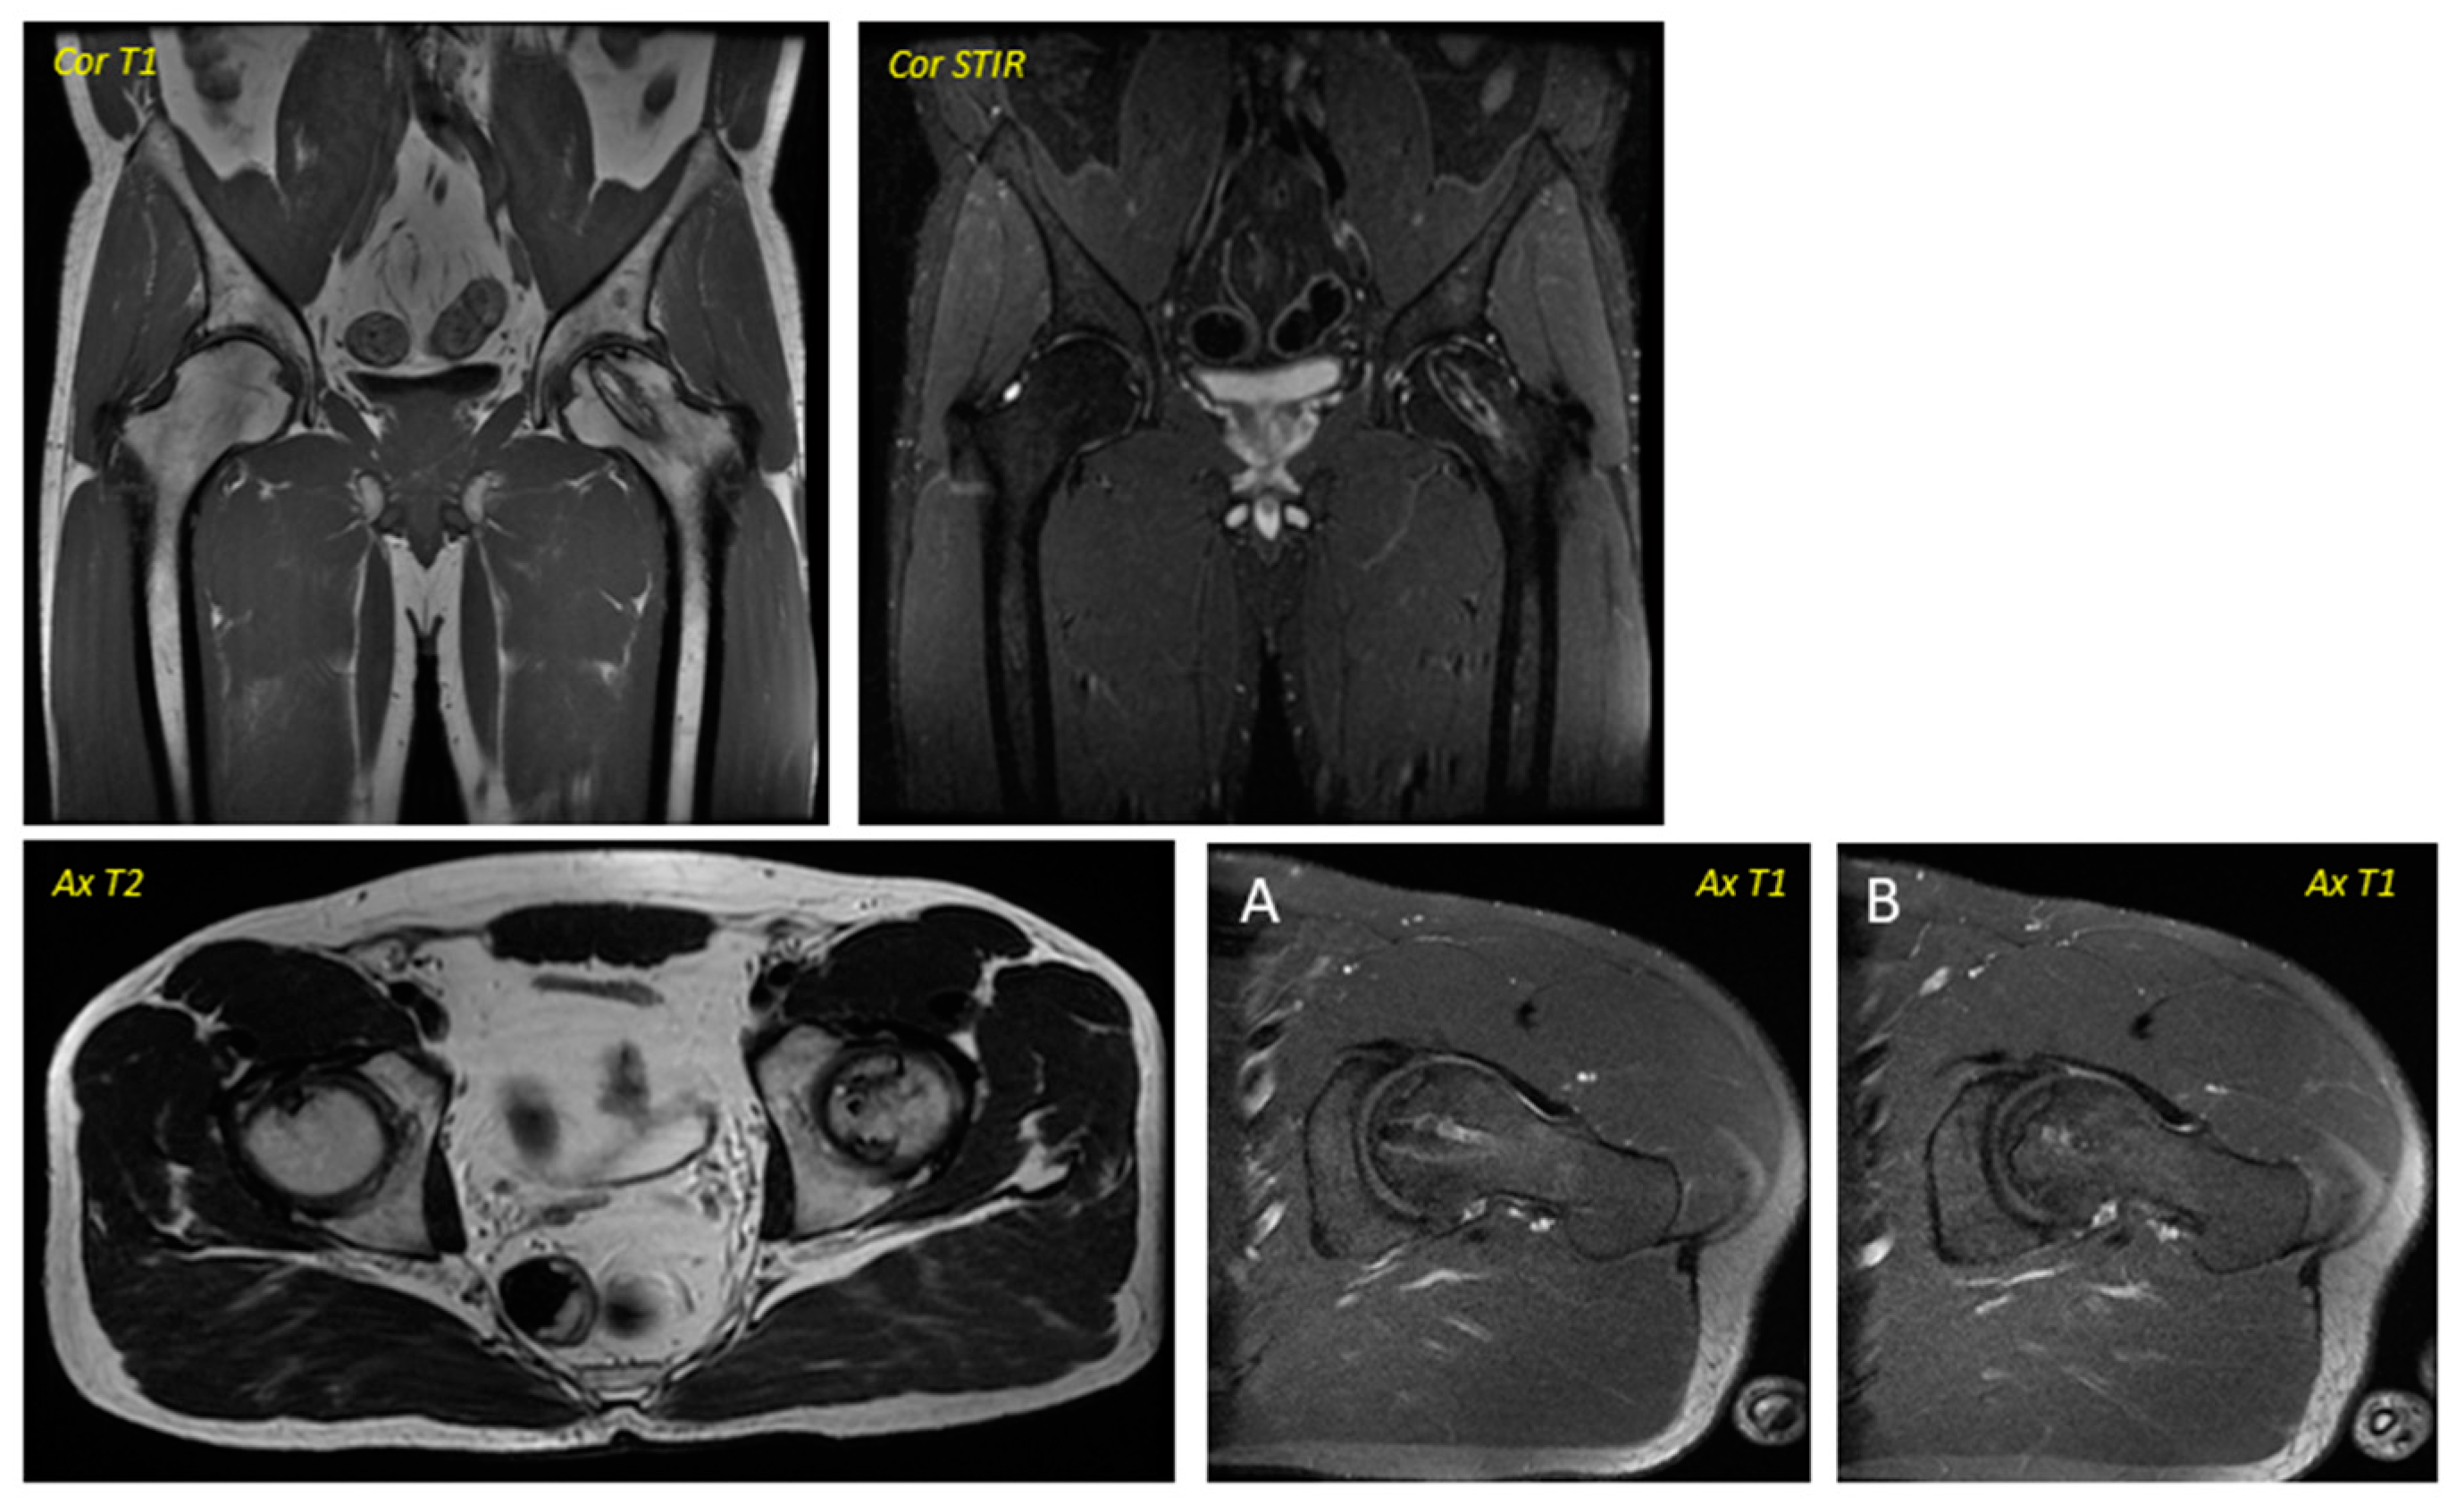

Figure 2. Post-surgical Magnetic Resonance Imaging corresponding to the patient in Figure 1 was performed in April 2016. Ax T1 (axial T1 plus contrast plus fat suppression–(A) Axial plus caudal incidence and axial (B) plus cranial incidence). Trocar entry is visualized in all images.

Regarding the imaging studies, several findings were observed in the radiographic evolution during the 12-month follow-up (Figure 1 and Figure 2). First, changes in the direction appeared in all cases from the sixth month, not being evident in earlier stages. Second, radiographic stabilization was achieved in 62.5% of the patients (n = 5) during the first year after surgery. Third, two patients (25%) showed the progression of the necrotic zone, while in one (12.5%), signs of re-ossification were evident. Despite observing descriptive differences, the p-value was not statistically significant for the latter parameter (p = 0.317).

Regarding the dynamics in the MR images, two patients were baseline in stage IA of the ARCO classification (25%), two in IIA (25%), and four in IIB (50%). In the same way, a stabilization in the staging of the post-surgery images was observed in seven of the eight patients studied (87.5%), with only one case (12.5%) evolving from grade IIB to grade IIIA, presenting subchondral collapse of the femoral head, which was already evident from the sixth month onwards. Descriptively, changes were observed, but they were not statistically significant. No significant variability was observed in the imaging findings between patients.